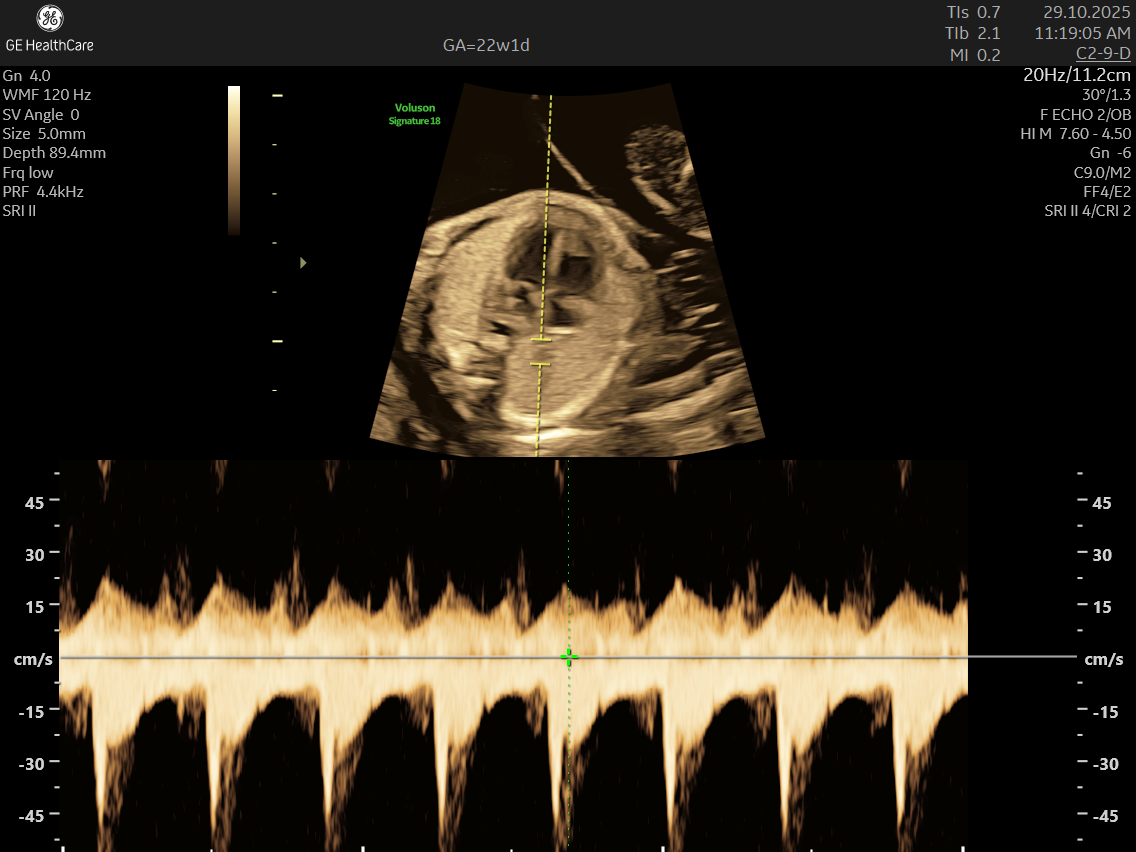

- Blood Flow Patterns: Detects arrhythmias or irregular heartbeats and checks for efficient circulation through the heart and major vessels.

- Rhythm Abnormalities: Detects irregular heartbeats or arrhythmias.

- Arrhythmias like premature atrial and ventricular contractions, supraventricular tachycardia, and complete heart block.

- Abnormalities in blood flow patterns and valve function observed on Doppler imaging.